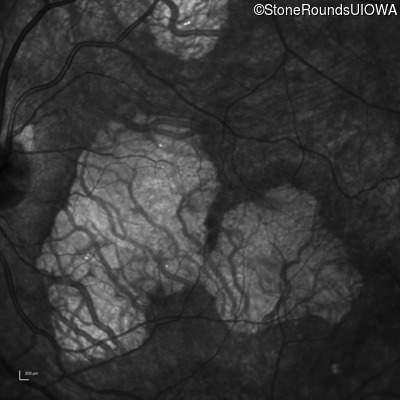

This 31 year old woman had subtle macular abnormalities discovered incidentally earlier that year. Her medical history at the time was unremarkable except for gestational diabetes during her most recent pregnancy. Five years later she was diagnosed with type 2 diabetes managed with oral medication. Two years later she developed sufficient hearing loss that hearing aids were required. Her acuity remained 20/20 OU at that time.